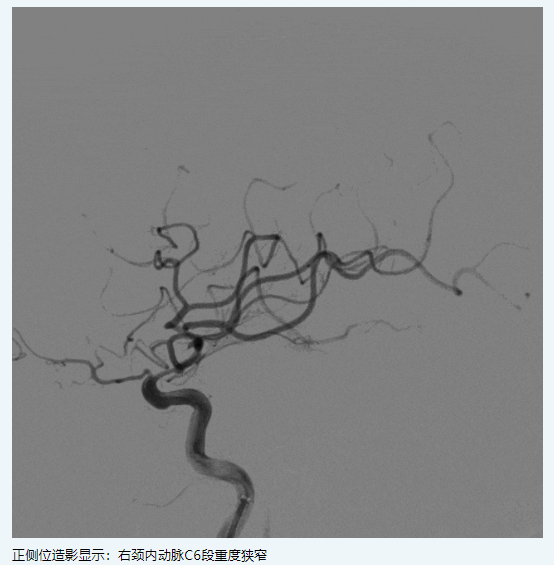

現(xiàn)病史:患者1月前因“左側偏癱,言語含糊”就診我科,溶栓后僅留有言語含糊(NIHSS評分1分)出院,出院診斷為“腦梗死,右側頸內(nèi)動脈C6段重度狹窄,高血壓病3級極高?!?,此次為進一步處理血管回診我科。

擬行手術方案:右側頸內(nèi)動脈C6段狹窄球囊擴張+顱內(nèi)藥物洗脫支架植入。

2.支架置入前應用小口徑球囊預擴張能降低動脈夾層及支架內(nèi)再狹窄的發(fā)生率。

4.頸內(nèi)動脈顱內(nèi)段迂曲,在此放置自膨閉環(huán)支架術后再狹窄發(fā)生率明顯比基底動脈和大腦中動脈升高,藥物洗脫球擴支架可能更適合這個部位的狹窄病變。

5.NOVA DES支架術后即刻血管成型效果好,術后再狹窄率低,但在曲度較大血管內(nèi)存在一定輸送難度,可采用“特洛伊木馬”技術,借助中間導管將支架輸送到位。